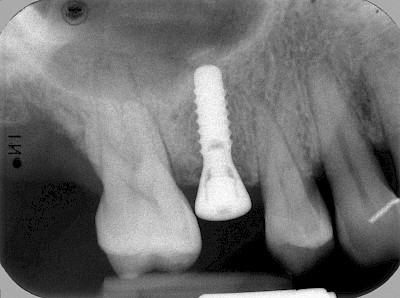

Implantate sind künstliche Zahnwurzeln – meist aus Titanlegierungen, selten auch aus keramischen Werkstoffen. Gehen Zähne verloren werden diese Implantate in den Kiefer eingebracht. Nach einer gewissen Einheilzeit (3-6 Monate) im Knochen wird zunächst für ein bis zwei Wochen das Zahnfleisch im Bereich die Durchtritts-Stelle "geformt" und in der Folge der sogenannte Aufbau (Abutment) aufgeschraubt. Der Aufbau erlaubt dann die Befestigung einer Krone, Brücke oder Zahnprothese.

"Stiftzahn" und "Implantat" ist nicht dasselbe! Bei einem Stiftzahn wird die Zahnkrone mit einem Stift in die noch vorhandene eigene Zahnwurzel zementiert. Ein Implantat im Gegensatz dazu ist selbst die (künstliche) Zahnwurzel, die dann weiter mit einem Zahnersatz versorgt wird.

In diesen Fällen kann die Planung mittels verschieden aufwendiger Röntgen-Techniken (Übersichtsaufnahme, DVT) ggf. unter Zuhilfenahme speziell angefertigter Planungsschablonen sinnvoll sein.